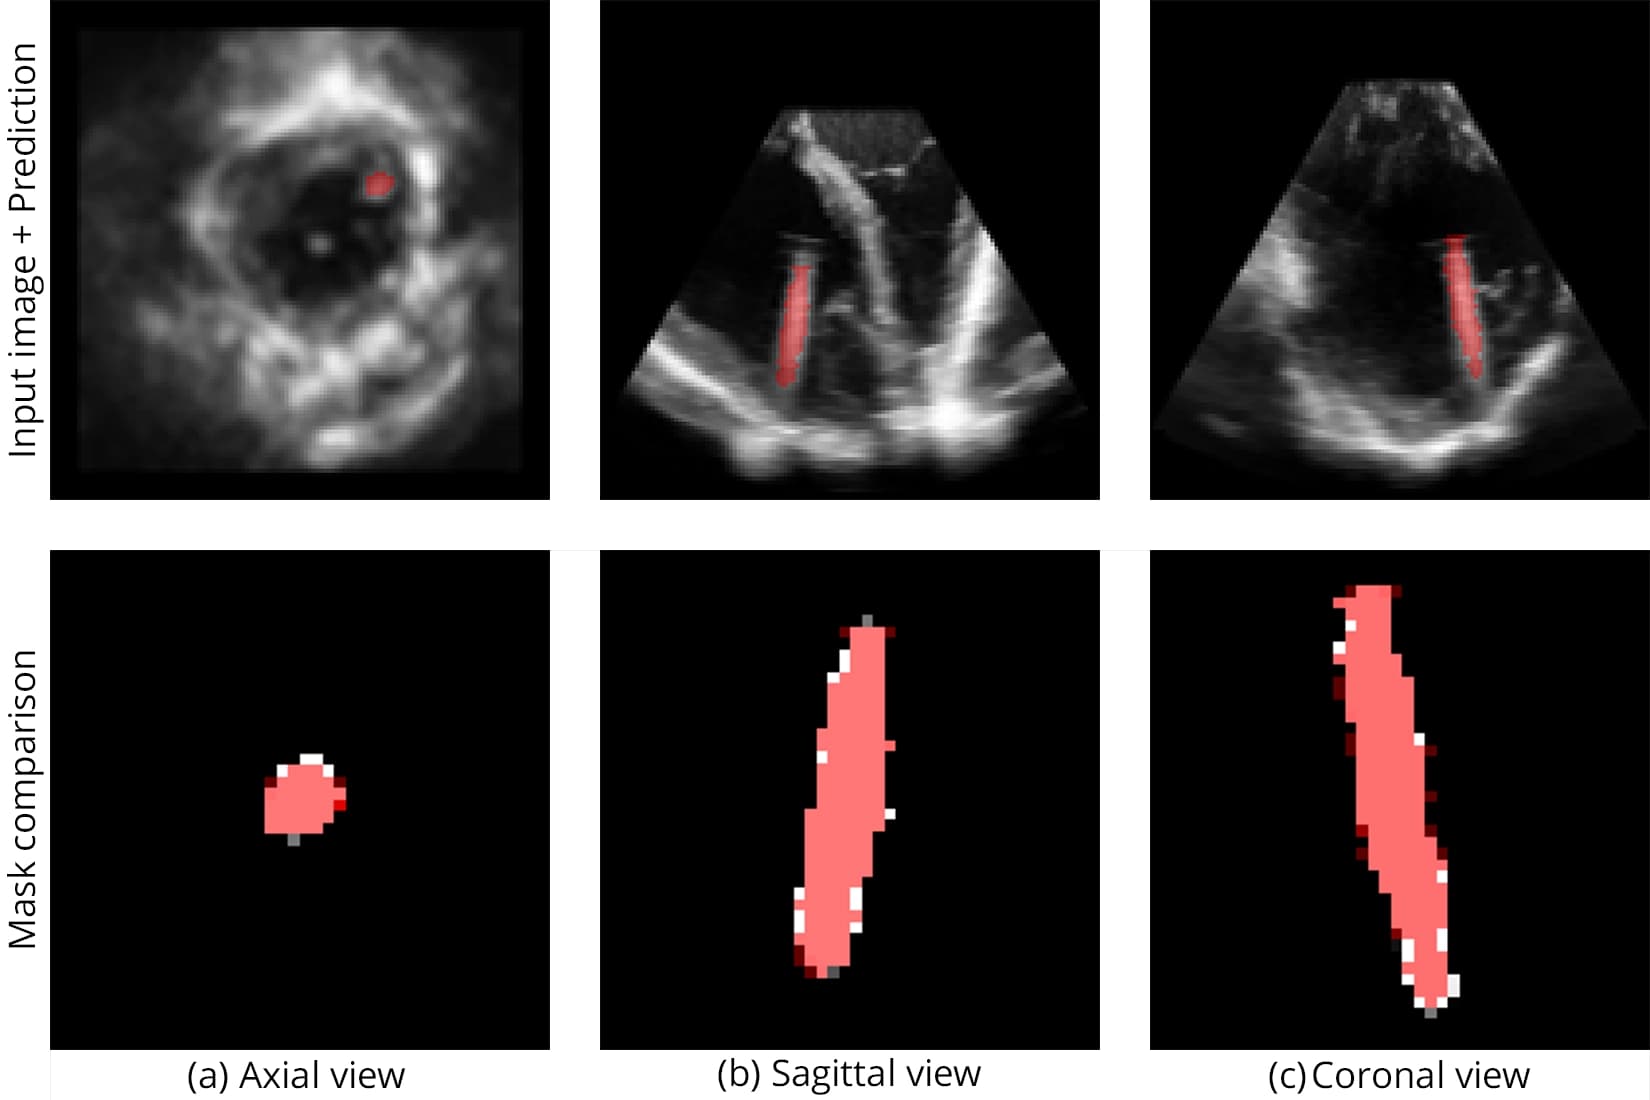

The catheter used in this study is shown in Figure 1, while Figure 2 illustrates the challenging visibility of catheters in raw ultrasound data.

The V-net architecture achieved high spatial precision in localizing catheters despite strong speckle noise and anatomical occlusion:

Segmentation accuracy on synthetic and real samples is shown in Figure 5 and Figure 6, and the comparison with other networks is presented in Figure 7.